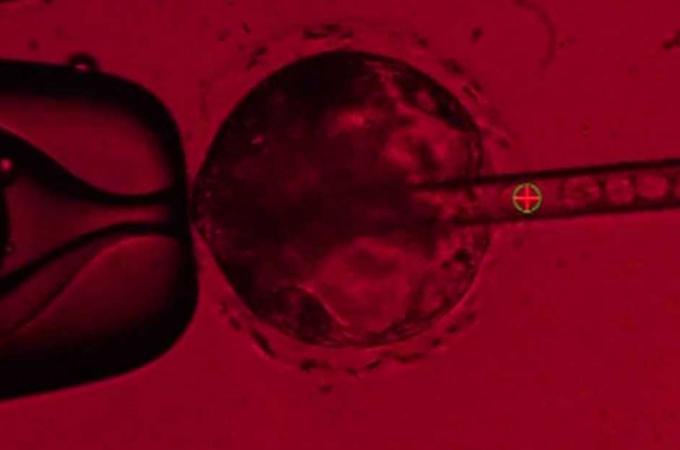

Průlom v medicíně: Britští vědci dostali zelenou pro editování lidských embryí